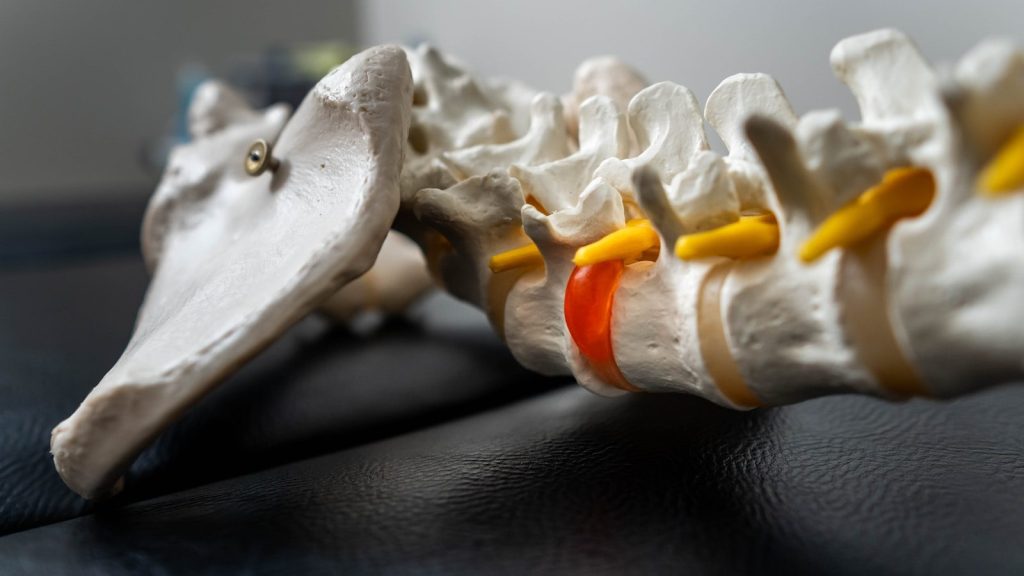

The body employs three distinct biological mechanisms to repair a ruptured disc, and these processes often work simultaneously to reduce both the structural problem and the associated pain.

Physical therapy is the cornerstone of conservative disc management. A qualified therapist designs a program that decompresses the affected spinal segment, strengthens the surrounding stabilizing muscles, and restores normal movement patterns.

McKenzie Method exercises, core stabilization training, and directional preference movements have all demonstrated strong outcomes for lumbar disc herniations specifically. Starting gentle movement early, rather than prolonged bed rest, consistently produces faster recovery in clinical evidence.